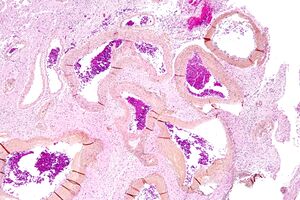

| صورة مجهرية لتشوه شرياني وريدي في المخ. HPS stain. | |

الشوه الشرياني الوريدي (إنگليزية: Arteriovenous malformation)، هو اتصال غير طبيعي بين الشرايين والأوردة ، متجاوزًا نظام الشعيرات الدموية . هذا الشذوذ الوعائي معروف على نطاق واسع بسبب حدوثه في الجهاز العصبي المركزي (عادة التشوه الشرياني الوريدي الدماغي ) ، ولكن يمكن أن يظهر في أي مكان. على الرغم من أن العديد من أنواع التشوه الشرياني الوريدي تكون بلا اعراض ، إلا أنها قد تسبب ألمًا شديدًا أو نزيفًا أو تؤدي إلى مشاكل طبية خطيرة أخرى..

نظرًا لأن التشوه الشرياني الوريدي يفتقر إلى التأثير الكابح للشعيرات الدموية على تدفق الدم ، يمكن أن يزداد حجم التشوه الشرياني الوريدي تدريجيًا بمرور الوقت مع زيادة كمية الدم المتدفق من خلاله ، مما يضطر القلب إلى العمل بجدية أكبر لمواكبة تدفق الدم الإضافي. كما أنه يتسبب في حرمان المنطقة المحيطة من وظائف الشعيرات الدموية - إزالة CO2 ـ إيصال المغذيات إلى الخلايا. لا يحتوي تشابك الأوعية الدموية الناتج ، والذي يُطلق عليه غالبًا بؤرة مرضية (كلمة لاتينية تعني "nest") ، على شعيرات دموية. يمكن أن يكون هشًا للغاية وعرضة للنزيف بسبب الوصلات المباشرة غير الطبيعية بين الشرايين ذات الضغط العالي والأوردة ذات الضغط المنخفض.[9] والعلامة الناتجة ، التي تُسمع عبر سماعة الطبيب ، هي صوت صفير إيقاعي ناتج عن تدفق الدم بسرعة مفرطة عبر الشرايين والأوردة. وقد أطلق عليه مصطلح "لغط" الضوضاء بالفرنسية . في بعض الحالات ، قد يدرك المريض المصاب بالتشوه الشرياني الوريدي الدماغي الضجيج ، مما قد يضر بالسمع ويتداخل مع النوم بالإضافة إلى التسبب في ضائقة نفسية.